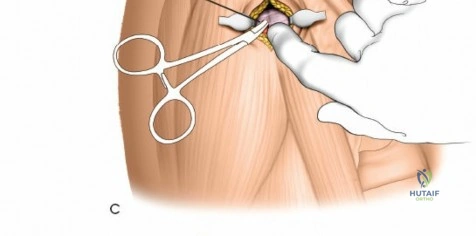

Humeral external fixation is most frequently utilized for damage control in polytrauma or for severe open fractures.

Proximal Humerus Pin Placement

1. Identify the safe zone on the lateral aspect of the proximal humerus, distal to the axillary nerve.

2. Make a longitudinal incision over the lateral aspect of the greater tuberosity or proximal diaphysis.

3. Bluntly dissect through the deltoid muscle fibers down to the bone.

4. Insert the drill sleeve, pre-drill with a 3.5 mm or 4.0 mm bit, and insert a 5.0 mm half pin.

5. Confirm bicortical purchase with fluoroscopy.

Distal Humerus Pin Placement

1. The distal pins are typically placed posteriorly to avoid the radial nerve.

2. Make a longitudinal incision over the posterior aspect of the distal humerus, proximal to the olecranon fossa.

3. Split the triceps bluntly down to the periosteum.

4. Insert the tissue protector, pre-drill, and place the 5.0 mm pins from posterior to anterior.

5. Ensure the pins do not penetrate the anterior cortex excessively to avoid injury to the brachial artery or median nerve.